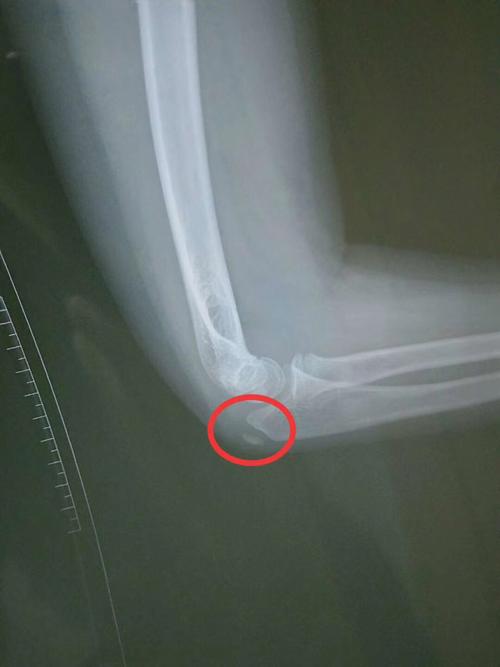

胳膊肘饶骨小头骨折,疑似鹰嘴也骨折,这是带支具一个月拍的片子,请问

请问大家,这张片子出,是骨折了吗?

尺桡骨中段骨折